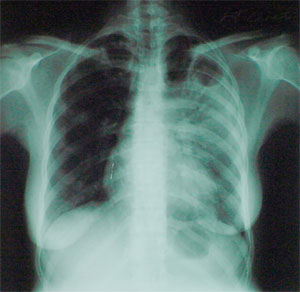

Луис Баррейро (Luis Barreiro) из Пастеровского института и его коллеги из Франции и Южной Африки провели генетическое обследование чернокожих жителей окрестностей Кейптауна (Южная Африка), среди которых уровень заболеваемости туберкулезом чрезвычайно высок. Выборка включала 350 больных и 360 здоровых индивидуумов.